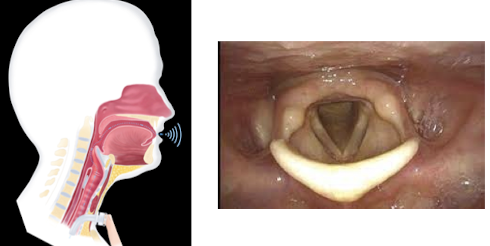

phonatory system

larynx

laryngeal tissue changes

Granulomas, vocal fold lesions, edema

Impact on glottic closure

loss of voice production

aphonia

dysphonia